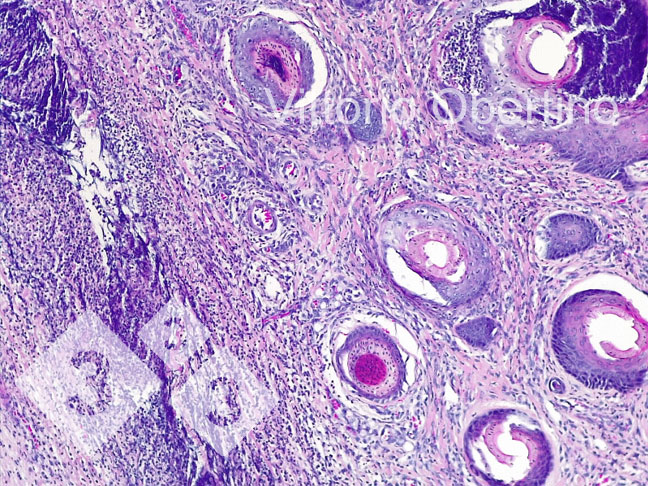

2- Próbki tkanek wysłano do Uniwersytetu w Turynie w celu sprawdzenia, czy zmiany histologiczne były zgodne z obrazami opisanymi w literaturze (Kuehling i wsp. 2020).

Rysunek 9. Skóra. Ogniskowa erozja nabłonka, w której warstwa powierzchniowa jest zastąpiona przez obfity, amorficzny lub ziarnisty materiał eozynofilowy ze szczątkami kariorektycznymi (martwicą) i licznymi zdegenerowanymi, żywotnymi granulocytami obojętnochłonnymi. Wieloogniskowo nabłonek wydaje się być od umiarkowanego do znacznego przerostu z umiarkowaną lub ciężką hiperkeratozą ortokeratotyczną. Obserwuje się również wieloogniskową obecność skorupy. Skóra właściwa wydaje się rozlana i umiarkowanie włóknista.